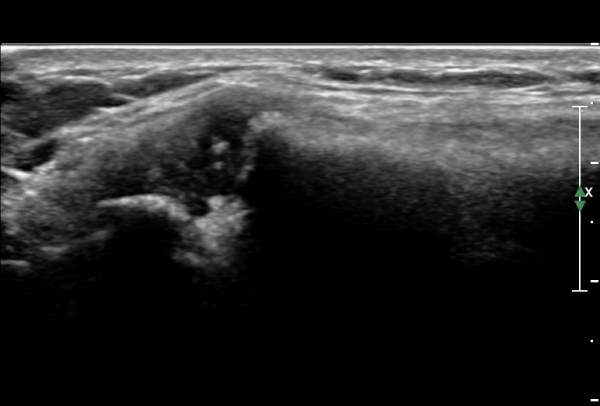

¿ìÃø Èä°ñ¼â°ñ°üÀýÃÊÀ½ÆÄ°Ë»ç¿¡¼­ °üÀýÀÇ ÅðÇ༭ º¯È­°¡ °üÂûµÊ(»çÁø 3, 4).